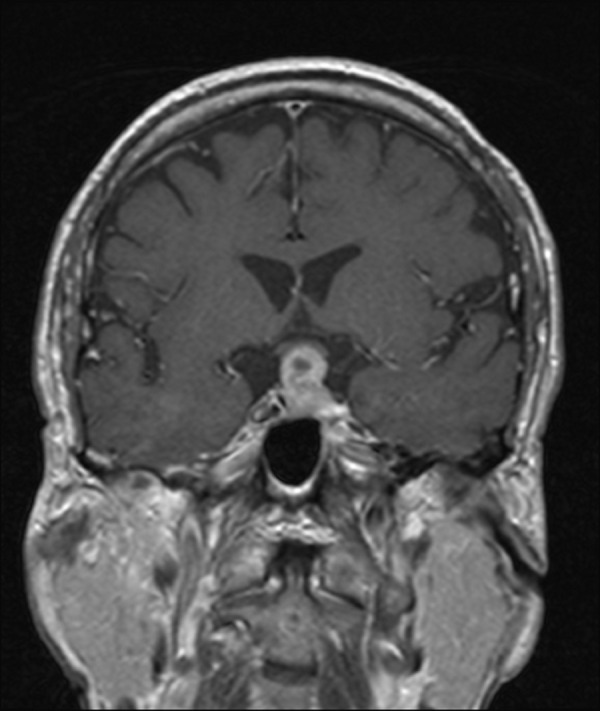

Figure 3. Follow-up MRI obtained approximately three and a half months following initial imaging .

T1 coronal MRI demonstrating complete resolution of the mass. The infundibulum is now visible and the optic chiasm is in its anatomic position.